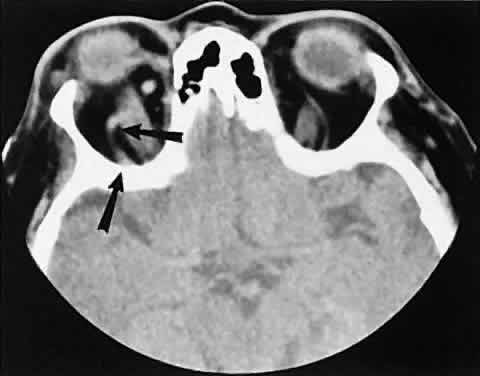

Perhaps the most common intracranial tumor to extend into the orbit is the meningioma. Those located along the spheroid wing tend to be associated with hyperostosis and tumor infiltration of the posterior lateral wall and roof of the orbit (Fig. 20). In our experience, isolated enlargement of the lateral rectus muscle is never caused by Graves' orbitopathy but rather is secondary to infiltration by spheroid wing meningiomas.

Fig. 20. Axial scan of a sphenoid wing meningioma showing an enhancing intracranial component (small arrows) with intraorbital extension. Note reactive hyperostosis of the sphenoid bone (large arrows).